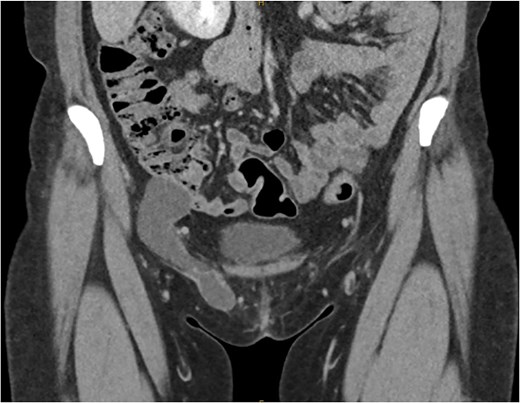

She proceeded for a laparoscopic TAPP excision of the hydrocele. After the abdominal cavity was entered and insufflated the preperitoneal flap was raised the hydrocele was identified medial to the inferior epigastric vessels (Fig. 2). With medial traction the hydrocele was able to be fully reduced and dissected free from the round ligament. The hydrocele was retrieved and sent for histological review. The resultant defect following excision (Fig. 3) was re-enforced with a 12 × 16 cm ProGrip mesh (Fig. 4) before the closure. She was observed post operatively and discharged home on the same day as her surgery.

Intraoperative image of the hydrocele (instrument overlying the inferior epigastric vessels.